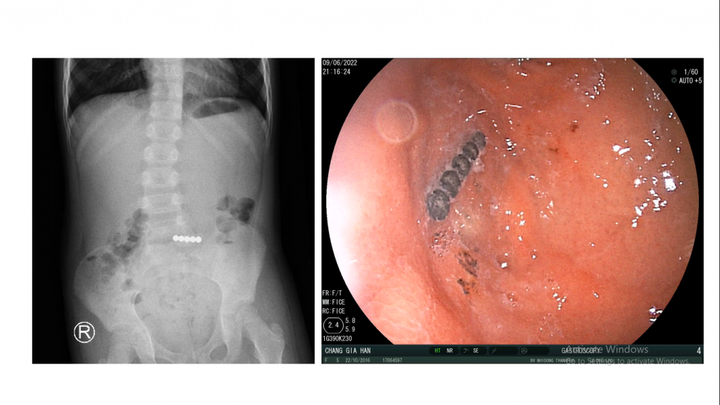

Tại bệnh viện, bé được hỗ trợ hô hấp thở oxy, chụp Xquang bụng phát hiện dị vật ở ruột non. Bệnh nhi được hội chẩn bởi các bác sĩ chuyên khoa tiêu hóa, bác sĩ ngoại khoa nội soi đường tiêu hóa cấp cứu và nội soi ổ bụng, đẩy dị vật từ ruột non lên dạ dày. Các bác sĩ gắp ra 5 viên bi nam châm dính liền nhau.

Hình ảnh dị vật trong ruột bé.